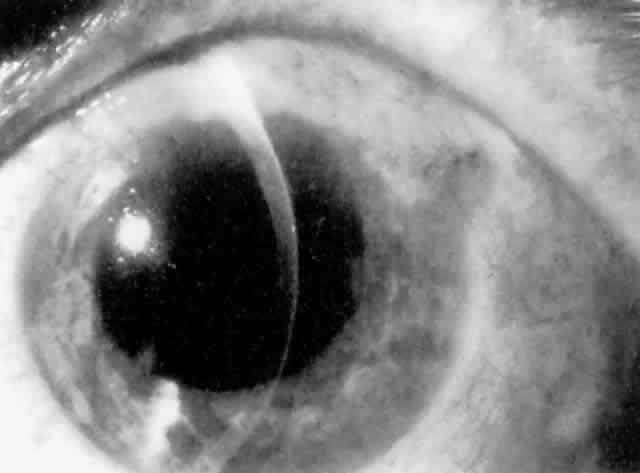

MANAGEMENT. The postoperative IOP elevation that occurs with the use of viscoelastic agents is exacerbated by cortical remnants and blood (Fig. 1). Careful cortical cleanup and aspiration of the viscoelastic agent may reduce the degree of IOP elevation. Prophylactic treatment of all patients (particularly those with preexistent glaucoma) with carbonic anhydrase inhibitors or beta-adrenergic blockers may decrease the incidence or severity of postoperative IOP elevation.35–38

Cortical lens fragments retained in either the anterior chamber or the vitreous can also obstruct the trabecular meshwork in the form of free lens particles or macrophages swollen with lens material (Figs. 2 and 3). Glaucoma does not occur in all eyes that contain cortical remnants; the inflammatory response may be more pronounced and prolonged in eyes containing a higher amount of lens material. When inflammation is marked, keratic precipitates and sometimes a hypopyon may be present. Distinction between this sterile inflammatory endophthalmitis and infectious endophthalmitis can be difficult and may depend on the initial response to therapy. The presence or absence of IOP elevation is not helpful in making this distinction because IOP may be normal or elevated in both situations.